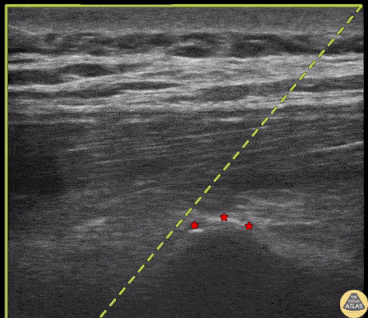

An erector spinae plane block is shown here, with the needle approaching in plane to touch the transverse process (*), and preparing to deposit anesthetic in the fascial plane between the transverse process and overlying erector spinae muscles. This block is generally best performed with the patient sitting facing away from the clinician, the US transducer in a parasagittal orientation just lateral to midline on the painful side, with an in plane approach, inserting the needle from the cranial or caudal aspect. Dr. Nhu-Nguyen Le, Fellow Denver Health Ultrasound Fellowship